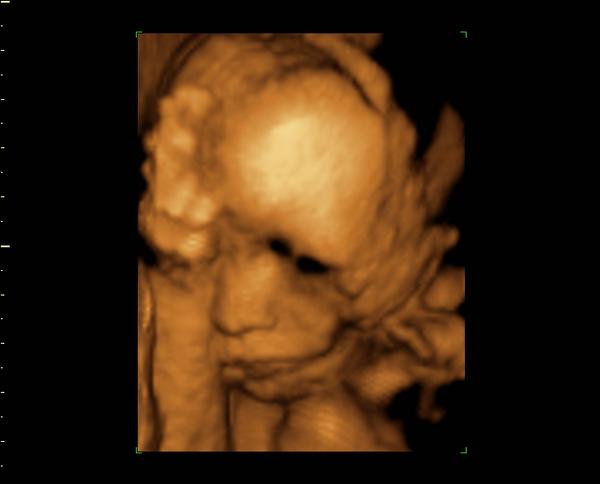

@darazv s dědečkem mě to mrzí,já už nemám ani jednu babičku ani dědečka. Máš pravdu,pokud jste oba zdraví,kašli na ivf...když se zadařilo u nás,povede se i tobě. Stejně na tom byla i petrufa a danielahe. Na miminko se oba moc těšíme, je to takový náš malý zázrak. Malá je čilá, kope jako o závod. Já jsem v pohodě, je mi dobře,probrala jsem zatím jen 3,5kg,vejdu se běžného oblečeni, prostě si to užívám.

@vormoni ahoj kočky, včerejší kontrola -vše v pořádku,malá má 1130 g, roste tak jak má. Dnes jsem objednala kočárek, už mám objednanou i postýlku a přebalovací komoru, do ložnice použijeme koš na kolečkách,ten je ještě po mně, jen jsem objednala novou matraci,mantinel a peřinky. Včera jsem jukla do HM a Spencera, mají slevy...cestou domů mě ještě zaujala deka do kočárku a lehátko do vany. Teď už jen nájezd na Ikeu pro žínky,osušky a matrací do postýlky a pak do lékárny a máme snad všechno.